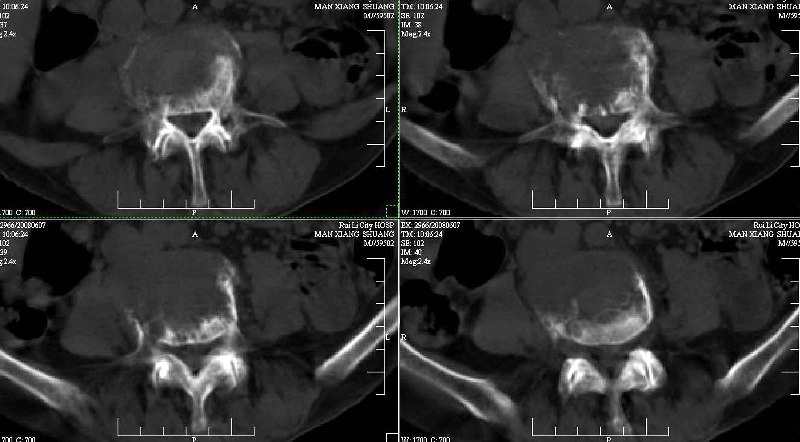

dr:l4骨质破坏,转移可能。

ct:肝癌腰椎转移。临床医生:肝脏、骨转移,肿瘤来自?前列腺?!

支持肝癌腰椎骨转移

腰椎间盘膨出+突出,椎体考虑为转移、退变。

建议强化观察肝内病灶特点,考虑肝癌骨转移。

支持肝癌伴椎体转移瘤。腹膜后建议ct增强,好象有增大的淋巴结。

1、支持肝癌肝内及腰椎转移。

2、肝脏内好象有多个病灶,建议增强检查。